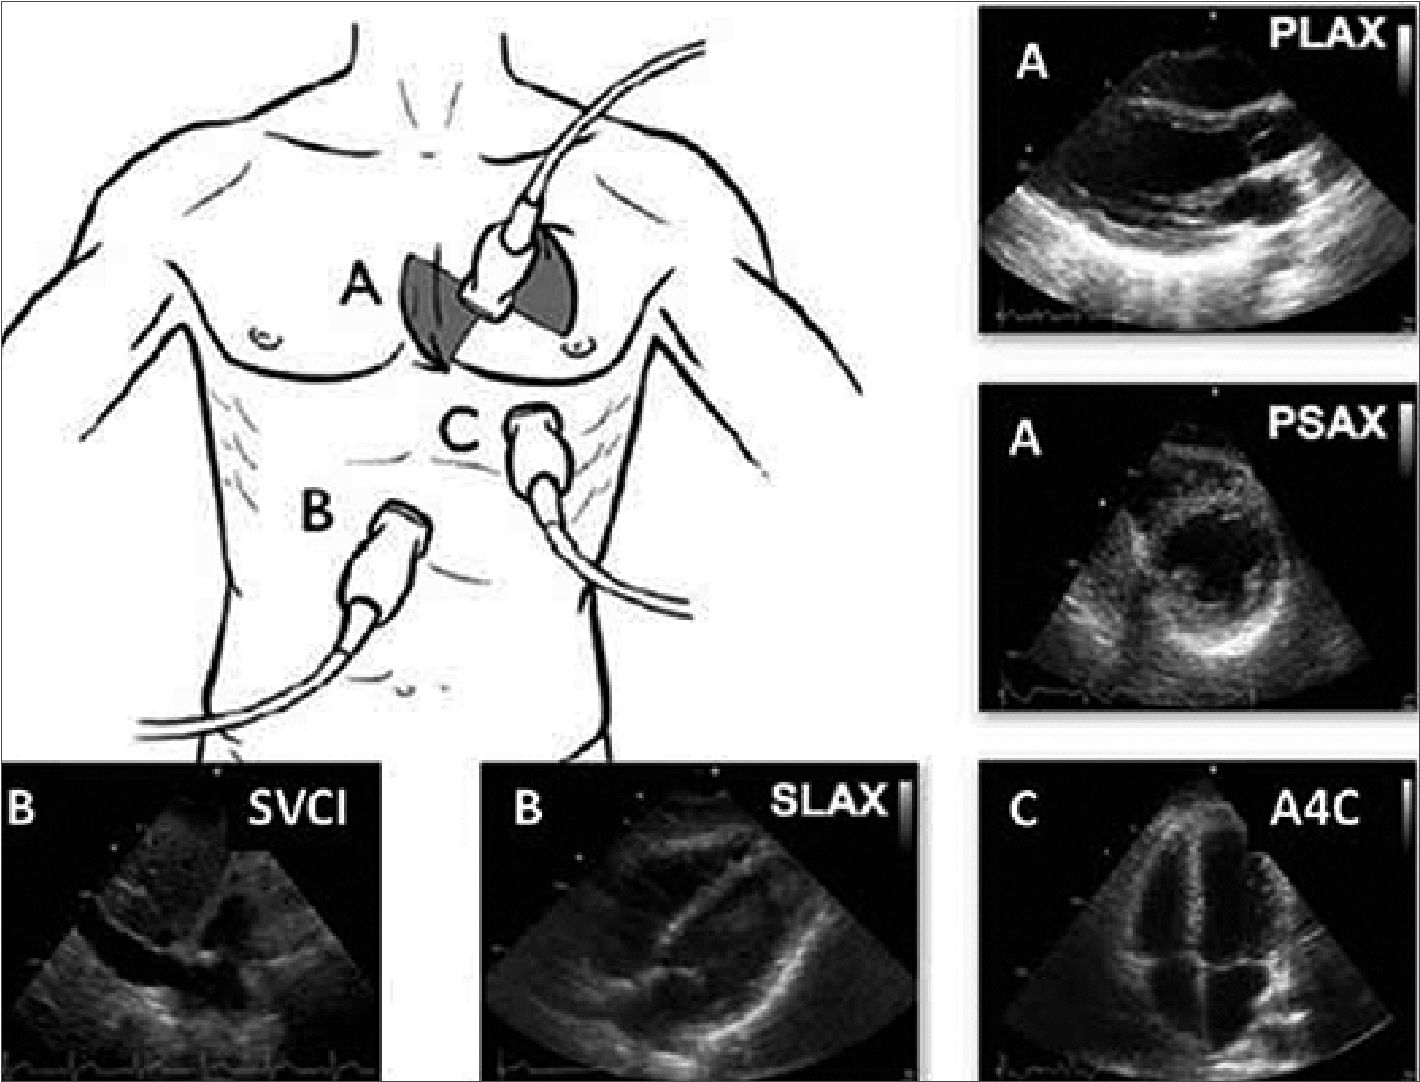

El FoCUS en pediatría se realiza con transductor sectorial y las ventanas básicas incluyen: Subcostal con visión de vena cava inferior (SIVC), (Figura 3), Subcostal 4 cámaras (S4CH), apical de 4 cámaras (A4CH), paraesternal eje corto (PSAX) (a nivel de músculos papilares) y eje largo (PLAX).

Figura 3. Ventanas y hallazgos en FoCUS. A) ventana paraesternal. PLAX: paraesternal eje largo, PSAX, paraesternal eje corto; B) ventaba subcostal; SVCI, subcostal vena cava inferior; SLAX, subcostal eje largo (también llamado subcostal 4 cámaras); C) ventana apical; A4C, apical 4 cámaras[20].